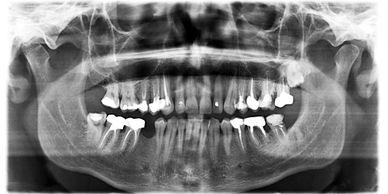

There are two types of dental x-rays you will come across: 1) Full mouth series/bitewings/periapicals, and 2) Panelipse (pano). Let's quickly breakdown the two and what the differences are.

During your initial visit your dental team will take a full mouth series of x-rays. This is a set of 18 x-rays (14 periapical's and 4 bitewings). This set of x-rays is completed only once every 3 to 5 years depending on your periodontal status. This full mouth set of x-rays will take individual radiographs (periapicals, or "PA's") of each tooth. The dentist is looking at your bone levels, sinsuses, infections and any abnormalities of the tooth and/or root structure. Changes in teeth usually are slow or chronic, this is why you take these x-rays less frequently, unless you have an emergency. In addition, 4 bitewing x-rays (see picture above), these are your cavity detecting x-rays. Changes in the density of your tooth enamel will show the dentist where cavities are.

You can expect an annual set of bitewings. Bitewings are very useful to catch dental caries ("cavities") early before they reach to far into your tooth.

Lastly, a panelipse ("pano"), may be taken during your initial visit or anytime during your dental life. A pano is a 360-degree radiograph used to check for any pathology, 3rd molars and advanced periodontal disease.